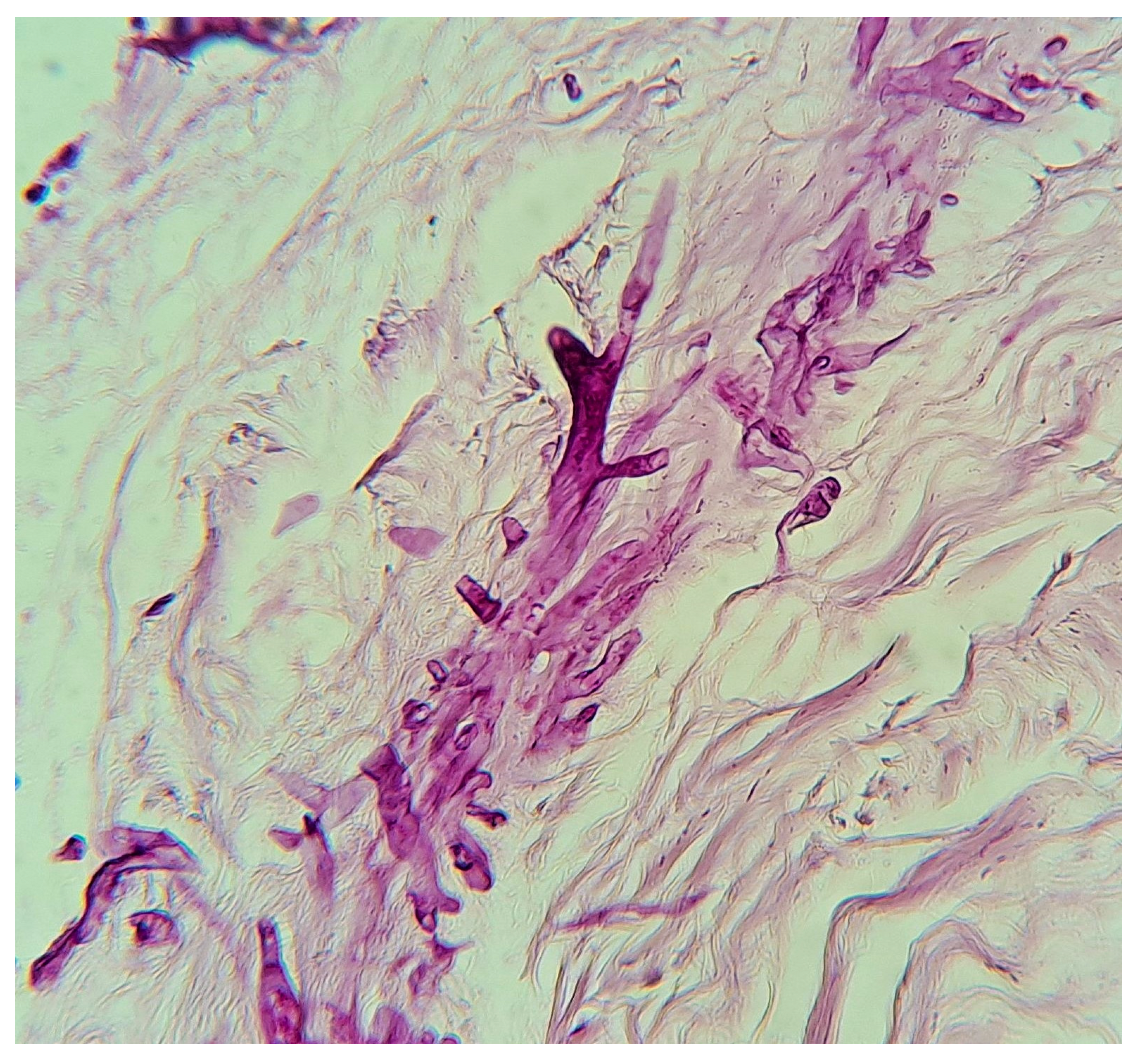

Formerly classified as zygomycetes, Mucorales have been reclassified to include the pathogenic genera Rhizopus, Mucor, Lichtheimia (formerly Absidia), Saksenaea, Rhizomucor, Apophysomyces, and Cunninghamella [1]. Among these, the most studied species are Rhizopus, Mucor, and Lichtheimia [1,2,3] (Figure 1).

Figure 1.

Microscopic study of Rhizopus spp. 40×, courtesy of Roberto Arenas.